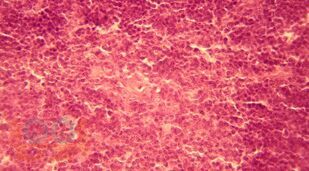

Монография посвящена результатам исследования возрастной морфологии тимуса в условиях воздействия дозированной гиподинамии и гипокинезии, которые можно использовать в различных разделах школьной гигиены, педиатрии, иммунологии, возрастной морфологии, в спортивной медицине.